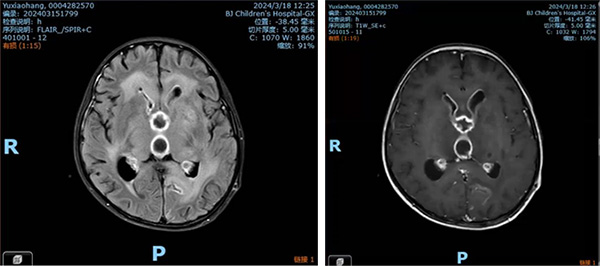

转眼间,2024年春节到来,本应是阖家团圆、充满欢乐的时刻,航航的病房却被紧张的氛围笼罩。大年初七清晨,航航突然呼吸急促、心率骤降,血氧饱和度急剧下降,甚至一度失去自主呼吸。张永湛住院医师及其他医护人员紧急展开抢救,待生命体征暂时平稳后,与影像中心联系,立即为其加做头颅MR检查。结果显示,双侧脑室室间孔堵塞,原有引流管仅能引流右侧脑室液,导致左侧脑室颅内压显著升高,危及生命,必须立即在左侧脑室置入引流管以缓解颅高压。

经过近2个月的全力治疗,航航脑室引流液中的脓液明显减少,脑脊液细胞学检查也有所改善,但他依旧反复发热,意识不清,头颅影像学显示颅内病灶未见明显好转,罕见感染难以控制的程度远超预期,整个脑脊液循环路径几乎都被真菌病灶堵塞,在儿童病例中极为罕见,药物治疗效果不佳,且因颅内感染部位分散无法手术切除病灶。这一状况让整个医疗团队一时陷入困境。

然而,航航的病情并未就此稳定。复查后的头颅影像检查显示航航颅内病灶再次恶化。中枢神经系统曲霉感染整体诊治难度大,死亡率超过65%,治疗时间长,强化期抗真菌治疗通常为8~12周,若病情平稳,还需进入后续9~12个月的维持期治疗。航航感染的罕见的真菌构巢曲霉治疗上更是难上加难。此时,航航已接受联合强有力的抗真菌治疗半年多,家属心急如焚,整个医疗团队也倍感压力。